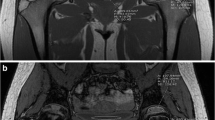

MRI acquisition included two-plane conventional T1-weighted spin-echo (TR/TE=624/9.7 ms), fat-suppressed T2-weighted (TR/TE=6,190/74 ms) and short tau inversion recovery (STIR; TR/TE=5,810/46 ms) sequences, and the multipoint Dixon technique as used for the animal specimens. All five children were scanned on 1.5-T scanners. The pelvis was examined in four cases and the spine in one. Regions of interest for the pelvis were placed along the posterior iliac crest, so as to be similar to the location for bone marrow biopsy. In the case of the spine MRI, the ROI was placed in the mid L5 vertebral body (Fig. 2). ROIs were placed using a clinical picture archiving and communication (PACS) station.

Imaging in a 10-year-old boy with metastatic rhabdomyosarcoma. a–c Axial T1 (a), axial short tau inversion recovery (STIR; b) and axial fat-only Dixon (c) MR images of the pelvis. Routine sequences show diffuse T1 hypointensity and STIR hyperintensity of the bone marrow. There is also abnormal soft-tissue signal surrounding the left iliac wing. The MRI fat fraction (FF) shows FF of 5%, or 95% cellularity, compatible with the marrow replacement process

Imaging in a 5-year-old girl with hip pain. a Coronal short tau inversion recovery (STIR) MR image shows diffuse hyperintense bone marrow signal. b Fat-only Dixon axial image with region of interest placed over the sacrum demonstrates fat fraction of 4%, or cellularity of 96%. Leukemia was confirmed with bone marrow biopsy